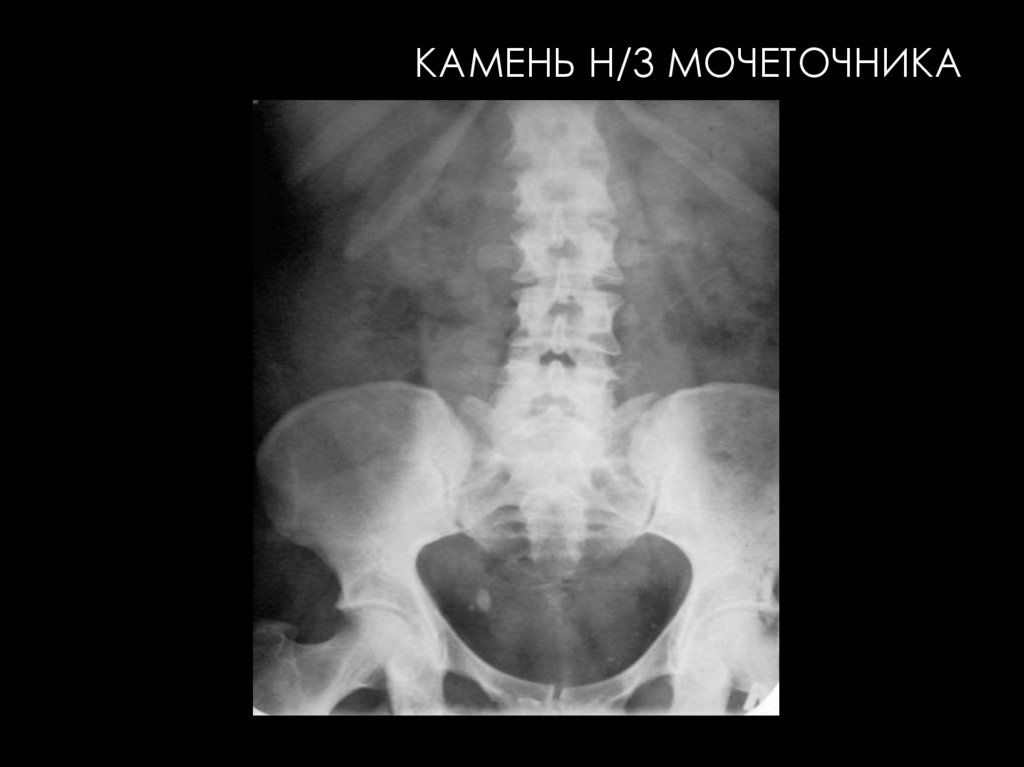

41.

КАМЕНЬ Н/3 МОЧЕТОЧНИКА

ОБЗОРНАЯ РЕНТГЕНОГРАФИЯ

На рентгенограмме могут

определяться дополнительные

образования

высокой интенсивности в проекции

почечных лоханок, мочеточников,

мочевого пузыря которые, как правило,

обусловлены конкрементами.